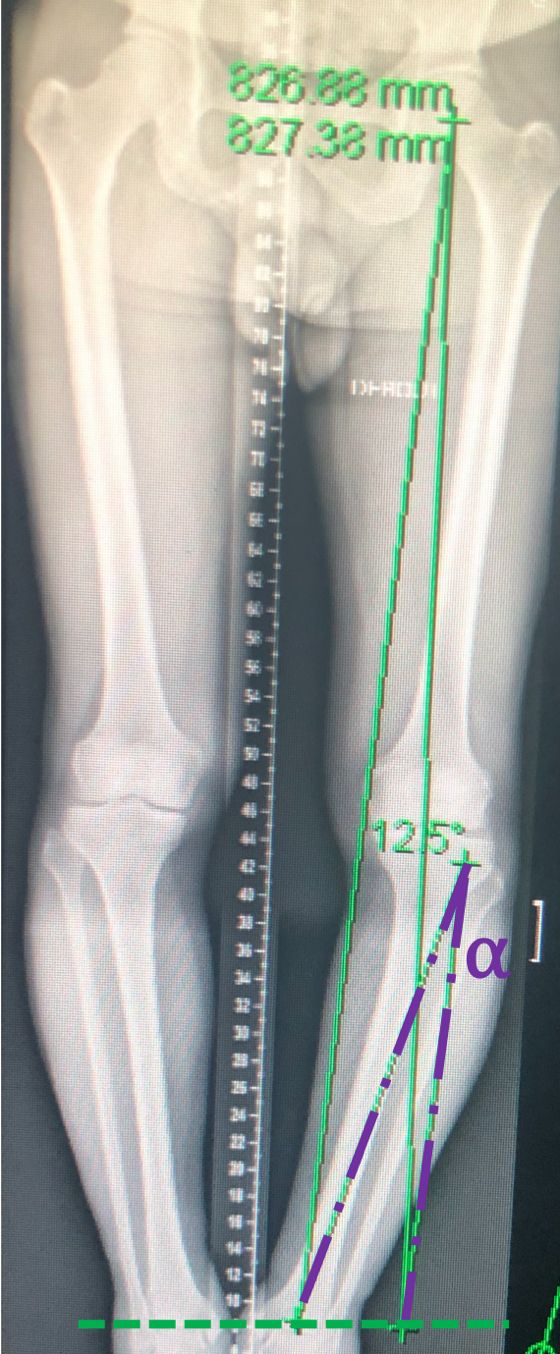

When dealing with a misaligned lower limb, the first step is to analyze if the deformity is located at the Tibia, Femur or both, which will influence where the osteotomy has to be performed. Not all varus knees have the deformity on the tibia only. 10-15% will need a femur or a combined femur and tibia osteotomy for correction, otherwise the jointline will be significantly malorientated. The next step is to decide for the proper postoperative frontal alignment and therefore to plan the desired correction. The planning must be performed on standardized full leg weight bearing X-rays [14]. Traditionally the new weight-bearing line should be within the “Fujisawa” point, which is 62% and 65% of the tibial plateau (with the medial side set at 0% and the outermost lateral aspect at 100%) [15]. Based on this point it is then possible to calculate the amount of correction needed in the frontal plane. One of the most common used technique for this correction angle α calculation is the Miniaci method [16] (Fig 1 D-E). Any existing soft tissue laxity on the concave side of the deformity (JLCA > 2 mm) has to be included in this bony correction angle calculation, otherwise the leg might be overcorrected.

The described conventional planning is focusing on the frontal plane only. PSCG includes the option of a much more sophisticated 3D planning procedure (Figure 1F).

This allows in more complex cases, osteotomies to be used for correction of ligament insufficiencies, treat intra-articular deformities or correct lower-limb torsional malalignments. In those cases, additional measurements are needed (Figure 2A-B).

For example, sagittal evaluation of the proximal tibia is mandatory to plan a slope modifying osteotomy in case of chronic cruciate ligaments insufficiencies or correction of sagittal bony deformity with a pathological slope. For ACL insufficiencies we reduce and for PCL insufficiencies we increase the natural slope. The aim of pathological slope correction is to end up with a normal value close to 7° [17]. Regarding varus deformities we usually aim for a correction of the Mikulicz line reaching a Fujizawa point between 55 to 65% based on cartilage and meniscus status. The CT scan included in the PSCG technique will also help surgeons to define quality and position of previous bone tunnels. For combined ACL reconstructions with OW-HTO the tunnel placement in reference to the screws can be planned also.